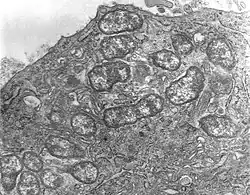

O. tsutsugamushi in human (U937) cells.

Orientia tsutsugamushi is a Gram-negative bacterium and is a permanent (obligate) parasite in mites. Within a single host cell, O. tsutsugamushi rapidly divides into many individuals. A unicellular organism, it is oval shaped and measures 0.5 to 0.8 μm wide and 1.2 to 3.0 μm long. Due to similarity, it was previously classified in the genus Rickettsia among other bacteria, but later assigned a separate genus, Orientia,[20] which it shares (as of 2010) only with Candidatus Orientia chuto.[21] It is broader but shorter than other rickettsial bacteria, which are rod shaped and on average measure 0.25 to 0.3 μm wide and 0.8 to 1 μm long.[22] During reproduction, it divides (by binary fission) into two daughter cells by the process of budding. While undergoing budding, it accumulates on the host cell surface, unlike other bacteria. One complete budding cycle takes 9 to 18 hours.[23]